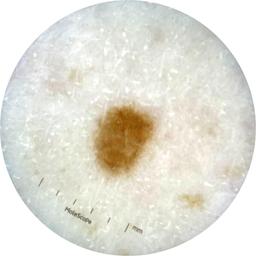

ISIC_9785574

Information

2003 x 2003

MEL-SELF Trial, https://www.sydney.edu.au/medicine-health/our-research/research-centres/melself-project.html

Field Value

acquisition_day 148

age_approx 45

anatom_site_1 Head and neck

anatom_site_general head/neck

concomitant_biopsy False

diagnosis_1 Benign

diagnosis_confirm_type single image expert consensus

family_hx_mm True

image_manipulation instrument only

image_type dermoscopic

lesion_id IL_0236417

patient_id IP_8456088

personal_hx_mm True

sex female